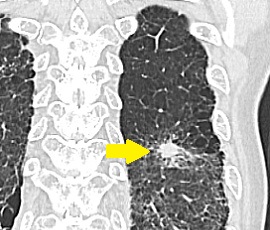

CT画像

CTガイド下針生検